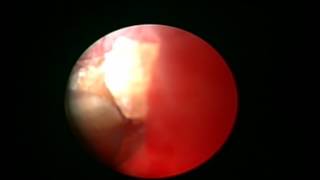

Μέθοδο TURis

Video Gallery